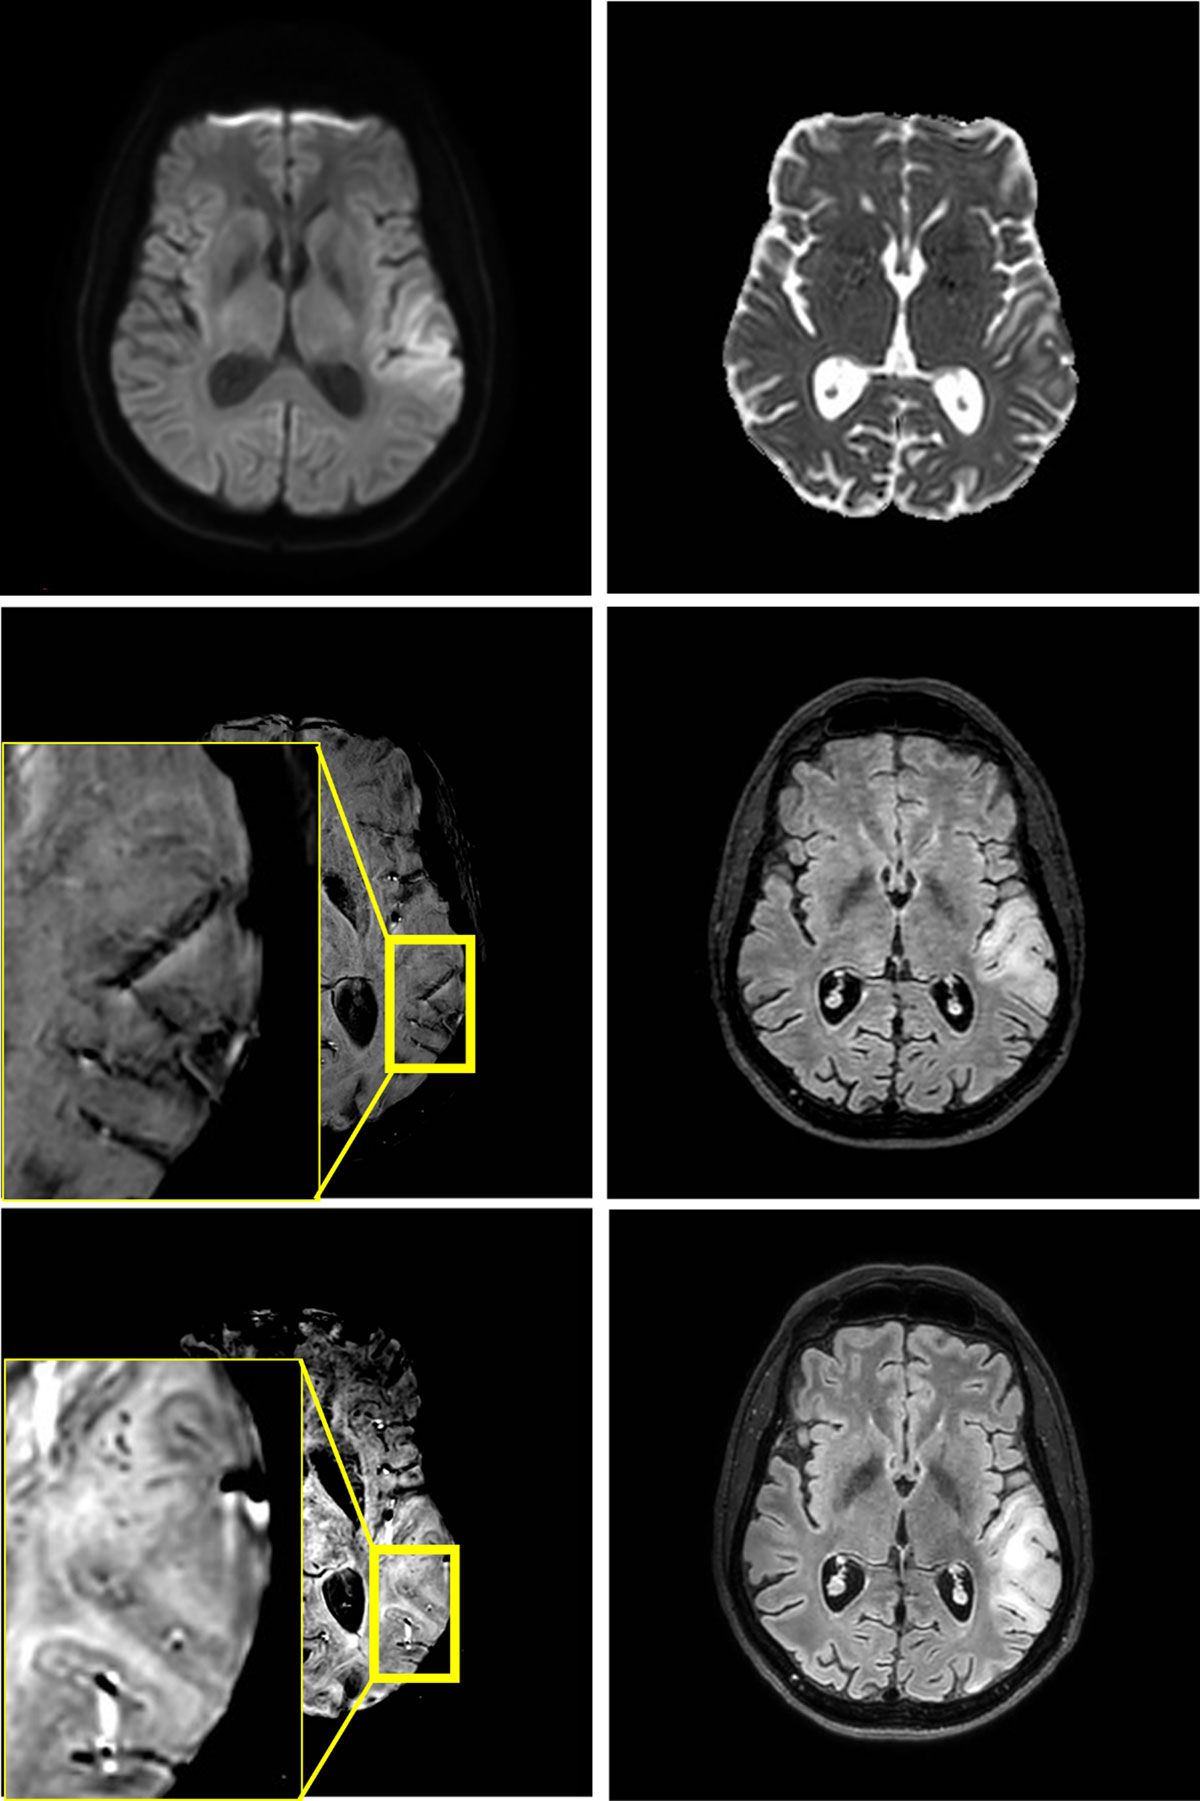

Figure 1

Edema in the left temporoparietal operculum without reduced diffusivity on MRI at 3T at first presentation (4 upper images). No microhemorrhages are found on the first scan, but they are present in juxtacortical location at one-week follow-up (2 lower images).